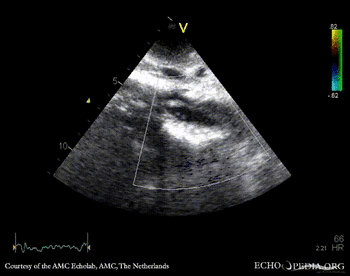

Subcostal view: mobile structure (thrombus) in abdominal aorta Subcostal view: mobile structure (thrombus) in abdominal aorta